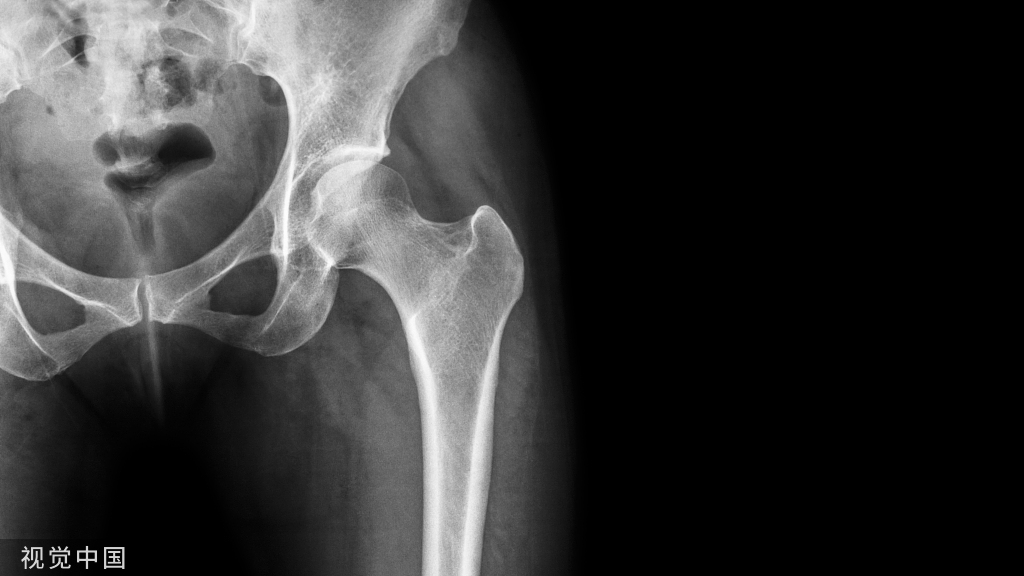

图:跟骨骨折,后关节面塌陷。

Gissane角:跟骨前后关节面之间的夹角,由跟骨外缘两条坚硬皮质骨柱的延长线构成,一条在后关节面的外缘,另一条位于前关节面的外侧,并向前延伸至跟骨前关节突的前部,正常范围在120-145°,该角度增大表明跟骨后关节面塌陷。

Böhler角:即跟骨结节关节面角。跟骨结节与跟骨后关节突连线,与跟骨前后关节突连线夹角,正常为35-45°。后关节面塌陷时该角减小。